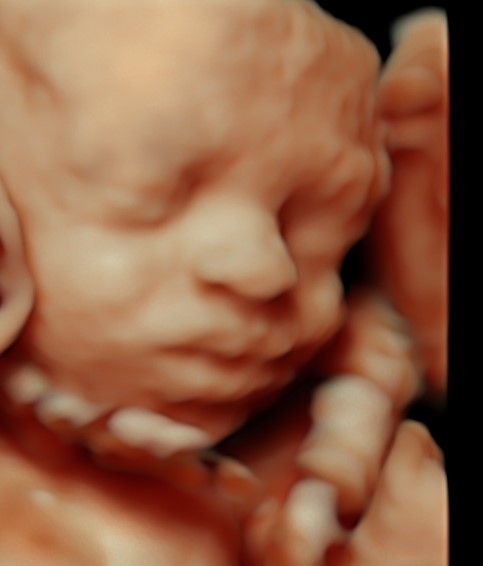

4D/5D/HD Ultrasound Gallery

Gallery